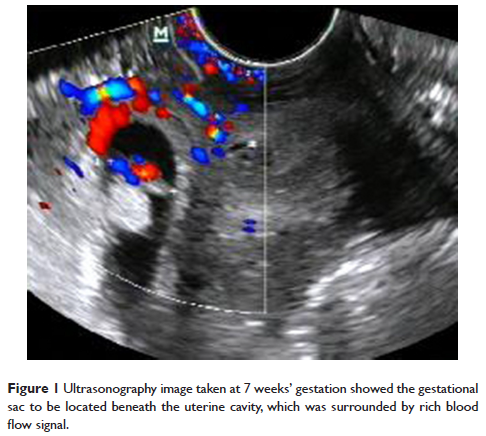

Case Report

- 作者:Shan-rong Shu, Xin Luo, Zhi-xin Wang, Yu-hong Yao

- 期刊:Therapeutics and Clinical Risk Management